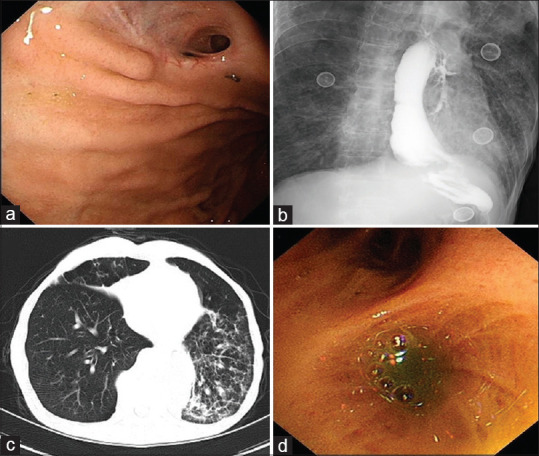

胃支气管瘘(GBF)是食管切除术后罕见但严重的并发症,具有很高的发病率和死亡率。硅胶塞的使用已被证明在其他情况下有效关闭支气管瘘,但其在GBF中的应用尚未被广泛描述。在本文中,我们报告了在支气管镜指导下使用自制硅胶塞成功关闭GBF的患者,该患者有食管癌食管切除术的历史。这种方法为治疗难治性GBF提供了一种安全、微创的替代方法。

Gastrobronchial fistula (GBF) is a rare but serious complication following esophagectomy, associated with high morbidity and mortality. The use of silicone plugs has proven effective in closing bronchial fistulas in other contexts, but its application in GBF has not been widely described. In this article, we report the successful closure of a GBF using a self-made silicone plug under bronchoscopic guidance in a patient with a history of esophagectomy for esophageal cancer. This approach offers a safe, minimally invasive alternative for managing refractory GBF.